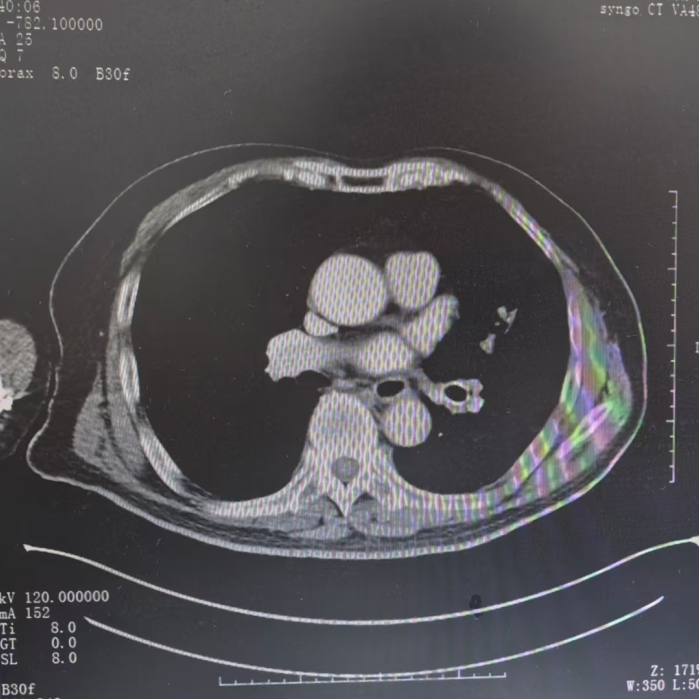

△做完射频消融术及支架置入术后,左肺基本复张

治疗后,庆叔叔左肺的炎症和肺不张均较前好转。为继续降低肿瘤负荷、局部灭活肿瘤,团队又为他施行了左肺部分肿瘤冷冻消融术。